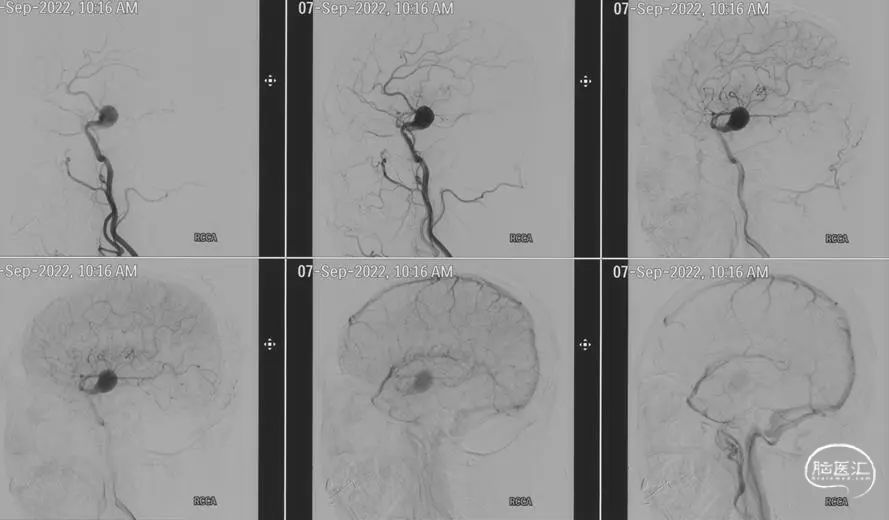

DSA(2022-9-7,我院):右侧大脑中大动脉瘤,瘤颈近侧M1狭窄约50%。大小19.1*16.1*15.2mm,宽颈,瘤颈远侧载瘤动脉呈明显梭形扩张,近分叉处直径3.1mm,瘤颈近侧载瘤动脉直径2.3mm。左侧椎动脉起始部中度狭窄。

图.3 右侧颈动脉正位DSA

图.4 右侧颈动脉侧位DSA